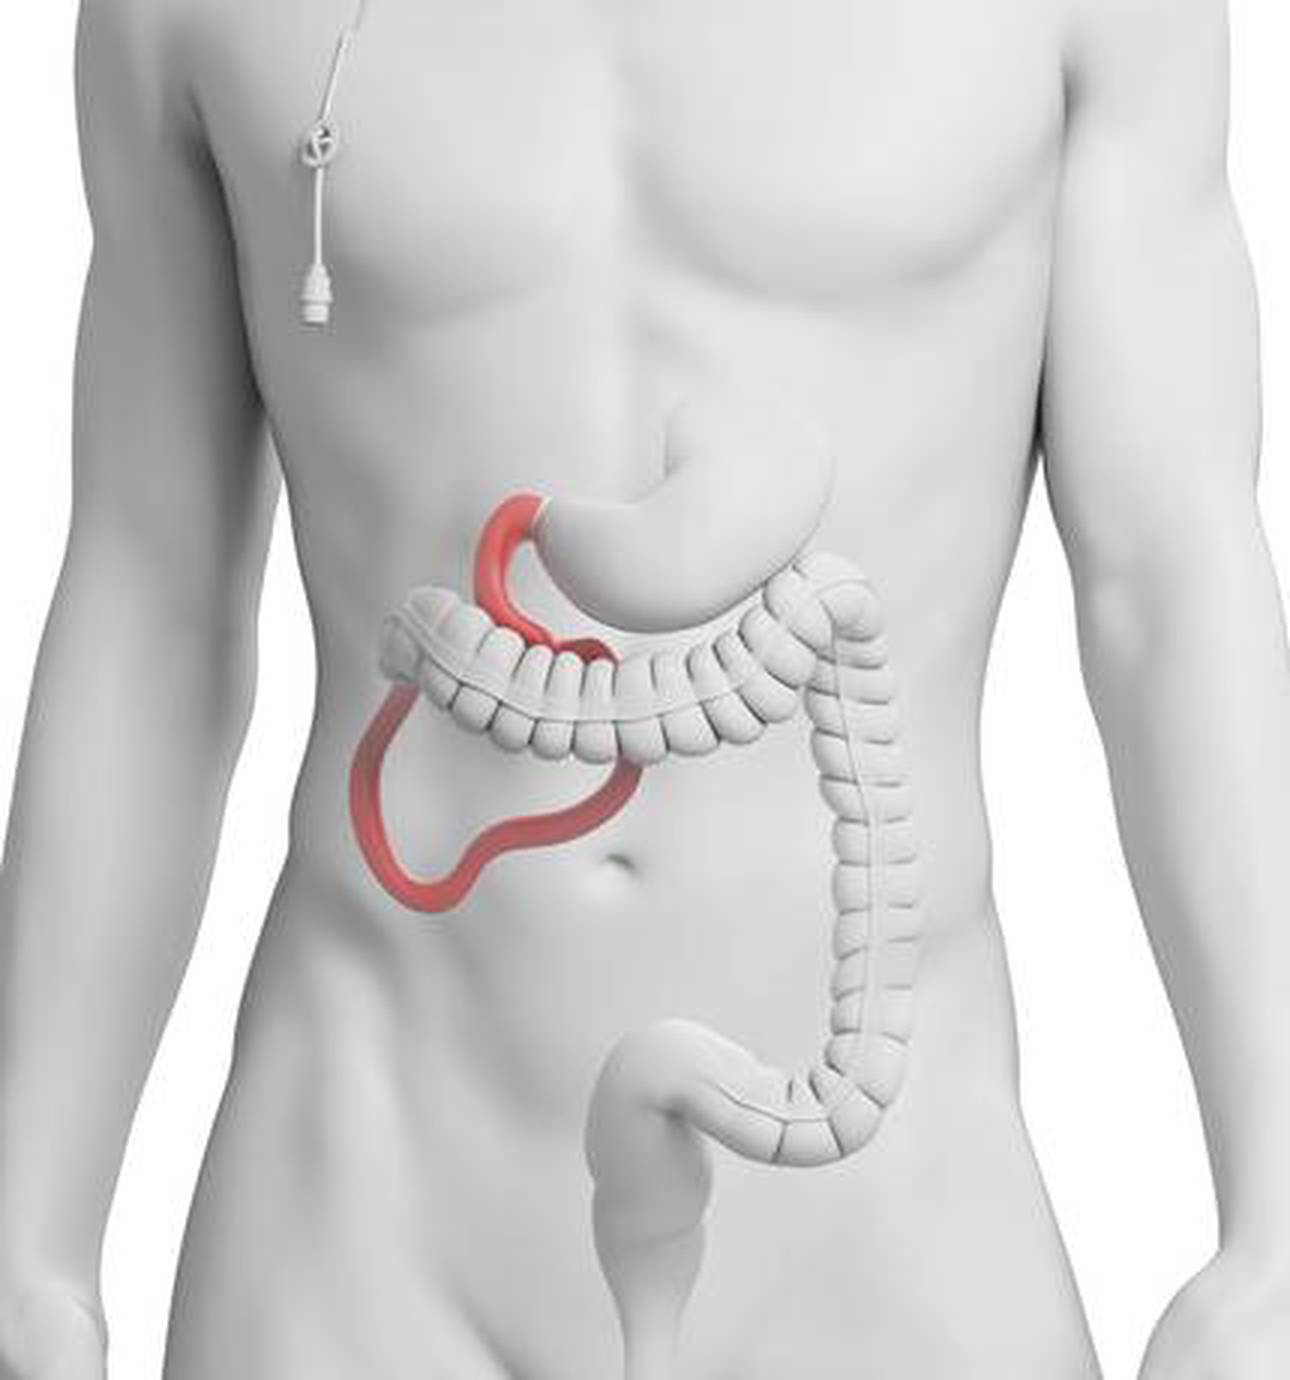

The Wolfson Unit for Endoscopy at St Mark’s Hospital is world renowned; being the only unit in the UK to achieve international recognition as a centre of excellence for endoscopy research and training.

The radiology department at St Mark’s provides access to a comprehensive group of investigations, using x-ray, ultrasound, CT and MRI to look at the abdomen and bowel.